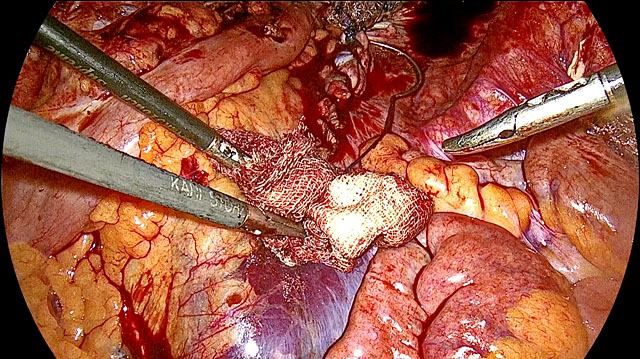

During tissue extraction, care should be taken to avoid spillage of myoma tissue, which can lead to peritoneal leiomyomatosis or port-site fibroid formation. This is best achieved through contained bag morcellation (Figure 10). Although the risk of inadvertently morcellating a leiomyosarcoma instead of a benign fibroid is extremely low, it remains a concern. In our experience, leiomyomas do not genetically transform into leiomyosarcomas, which are de-novo malignancies that can arise from any smooth muscle tissue.

10

Contained-bag morcellation for myomectomy. (a) Stomach-shaped sterile bag. (b) Bag folded and inserted through the hole in the tail of the bag. (c) The tail is forced into the primary trocar. (d) The trocar is inserted into the bag from the hole in the tail. (e) The large myoma is enclosed within the bag, which is then closed. (f) The mouth of the bag is exteriorized from the left lower port. (g) The morcellation process. (h) >2-kg specimen of morcellated myoma tissue. (i) Postmorcellation, the mouth and tail of the bag are seen. (j) The tail is tied and the mouth grasped for removal.